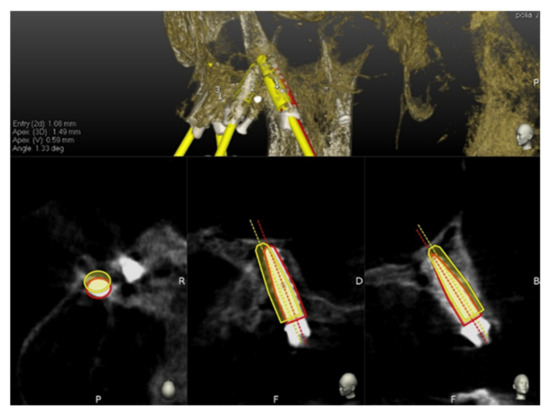

After tracing all selected landmarks/teeth, the software automatically performs the registration process. The sample traced points are aligned with strong edges in the CBCT image. The complete trace and registration process takes 1–2 min on average. The accuracy of the trace registration can be evaluated instantly in the software by touching the patient’s teeth with the tracer’s ball tip from the buccal, lingual, incisal/occlusal and proximal planes and comparing the actual physical location of the tracer tip with its own on-screen representation on the system’s display (Figure 3 and Figure 4). The same check can also be carried out in edentulous cases by touching bone screws intentionally placed before taking CBCT scan. If the registration accuracy is not satisfying, the tracing step can be immediately repeated.

Figure 4. The surgeon can then verify the registration accuracy by touching with the tracer’s ball tip on the patient’s landmark from several aspects and comparing the physical location of the tip with its on-screen representation on the system’s screen.